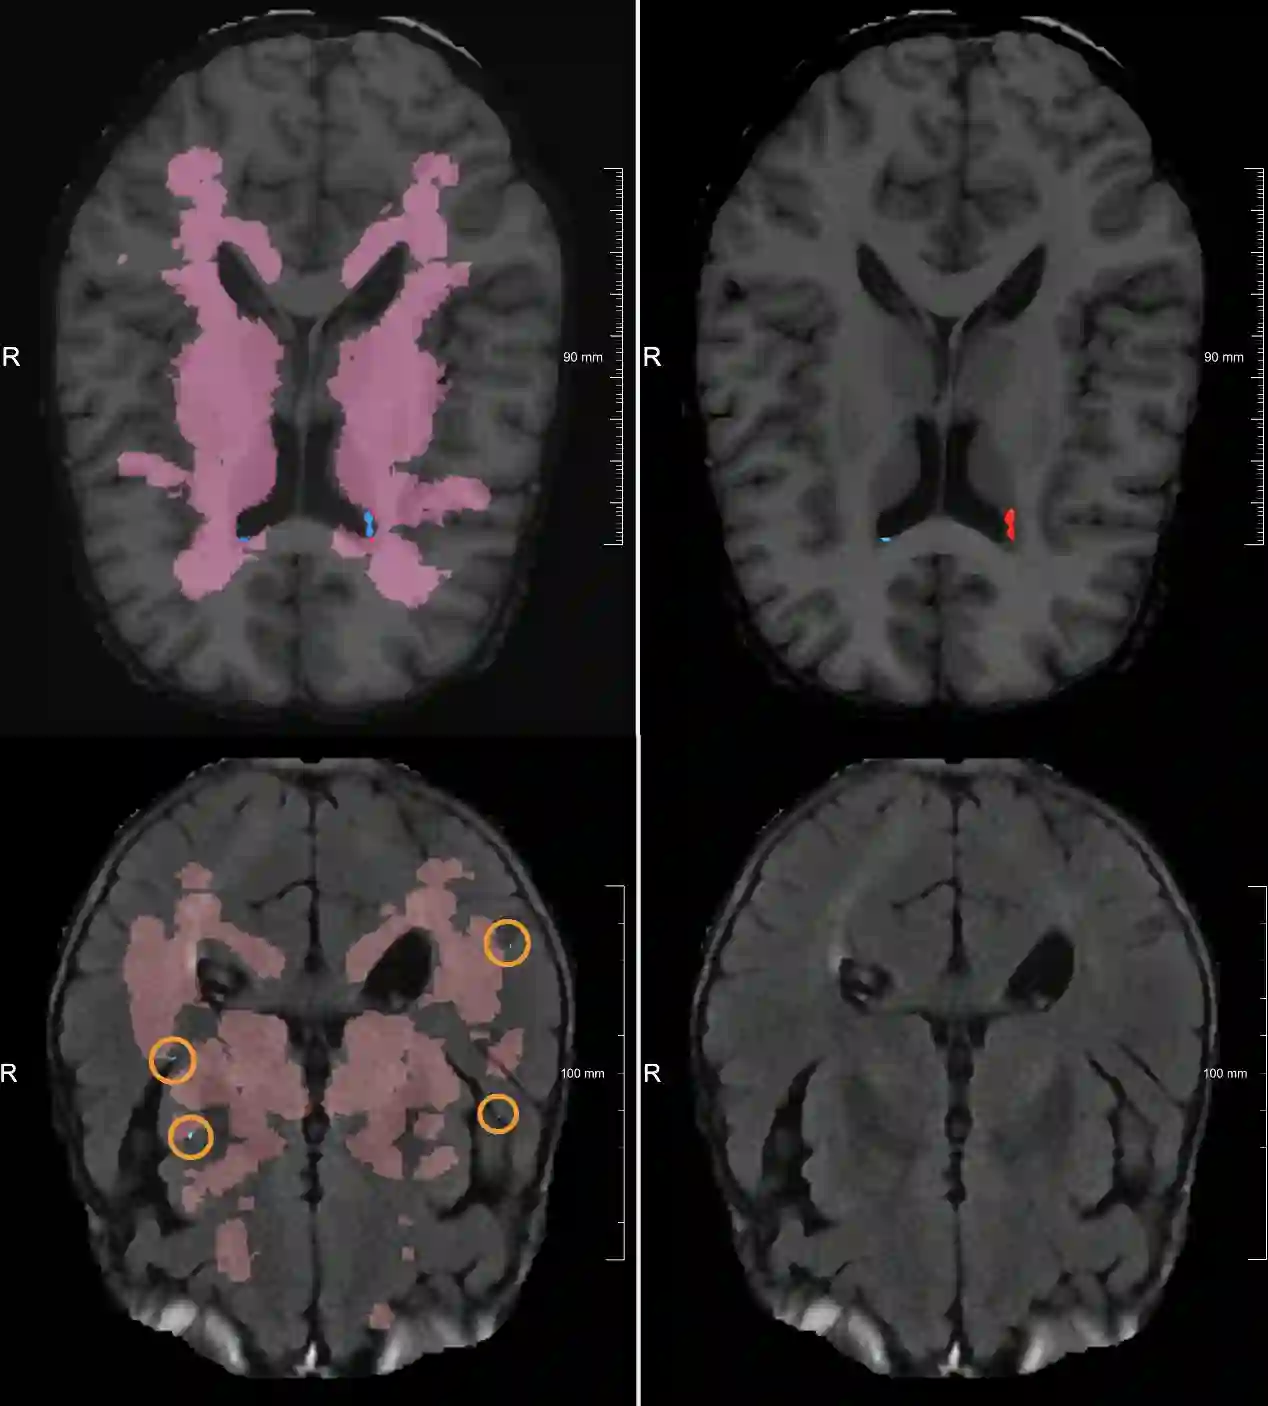

Lacunes of presumed vascular origin are fluid-filled cavities of between 3 - 15 mm in diameter, visible on T1 and FLAIR brain MRI. Quantification of lacunes relies on manual annotation or semi-automatic / interactive approaches; and almost no automatic methods exist for this task. In this work, we present a two-stage approach to segment lacunes of presumed vascular origin: (1) detection with Mask R-CNN followed by (2) segmentation with a U-Net CNN. Data originates from Task 3 of the "Where is VALDO?" challenge and consists of 40 training subjects. We report the mean DICE on the training set of 0.83 and on the validation set of 0.84. Source code is available at: https://github.com/hjkuijf/MixLacune . The docker container hjkuijf/mixlacune can be pulled from https://hub.docker.com/r/hjkuijf/mixlacune .